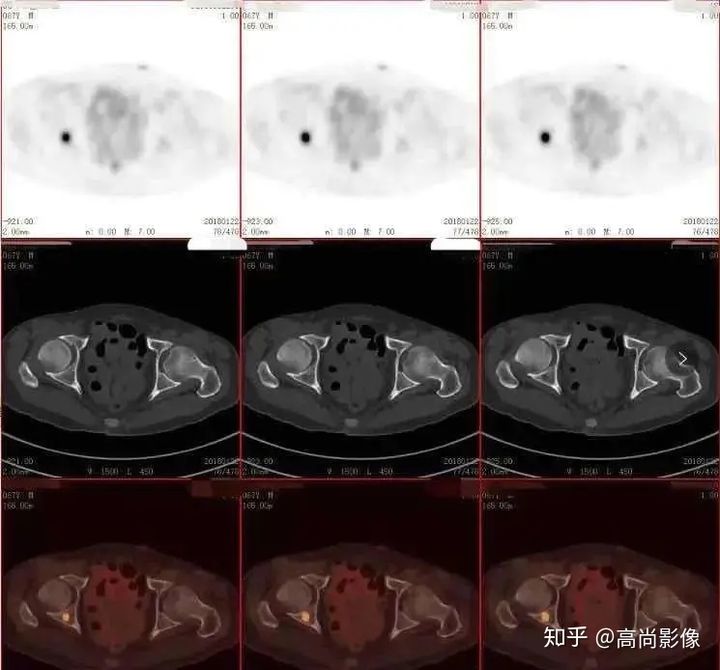

(胸椎骨轉(zhuǎn)移合并病理性骨折)

(右側(cè)髖臼骨轉(zhuǎn)移)